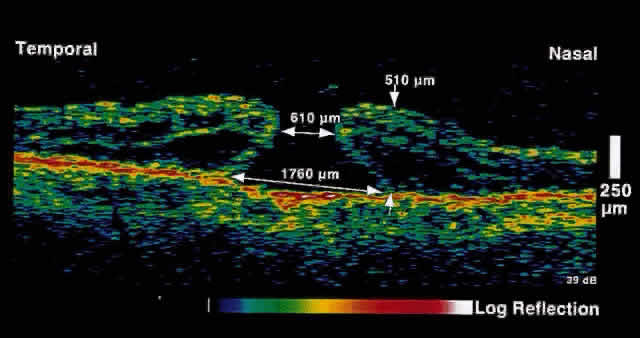

resolution of macular edema after laser treatment may be observed (Figs. 5 and 6).  Fig. 5. OCT image through the fovea of a patient with clinically significant macular

edema. Fig. 5. OCT image through the fovea of a patient with clinically significant macular

edema.

|